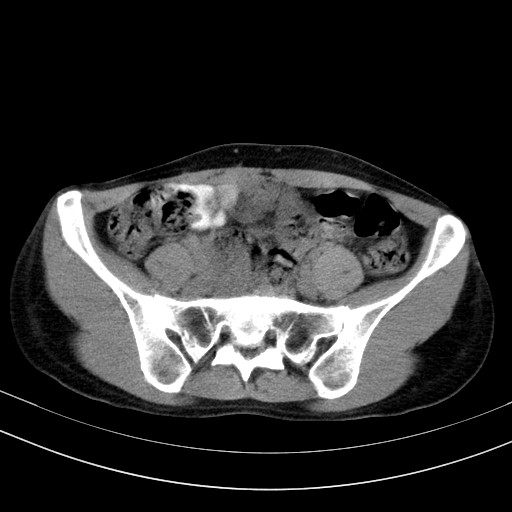

以下是引用随光逐影在2009-4-7 8:17:00的发言:[br]考虑宫颈占位性病变(宫颈癌?);建议行进一步检查。

以下是引用jiangjing在2009-4-7 16:46:00的发言:[br]宫颈增大,结构不清,右侧附件区可疑囊样占位,建议增强及mri 检查